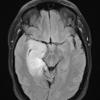

Astrocytoma, IDH-mutant, WHO Grade 2 (2)